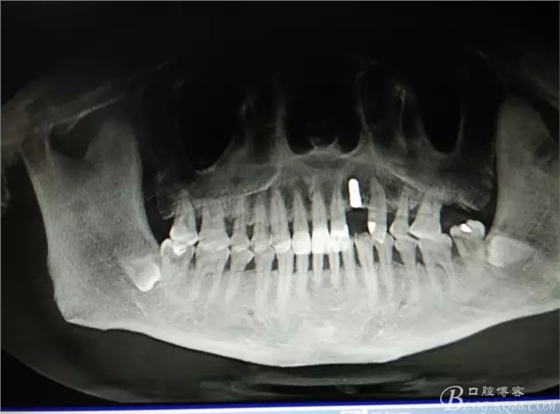

患者、楊xx、男、49歲。主訴:左側(cè)前牙拔除半年,活動義齒修復(fù)四個月,要求種植修復(fù)。??茩z查:21缺失,牙槽粘膜厚度正常。CBCT檢查:高度16mm,寬度7mm.術(shù)前簽知情同意書。

圖1.術(shù)前的CBCT檢查:22缺失。